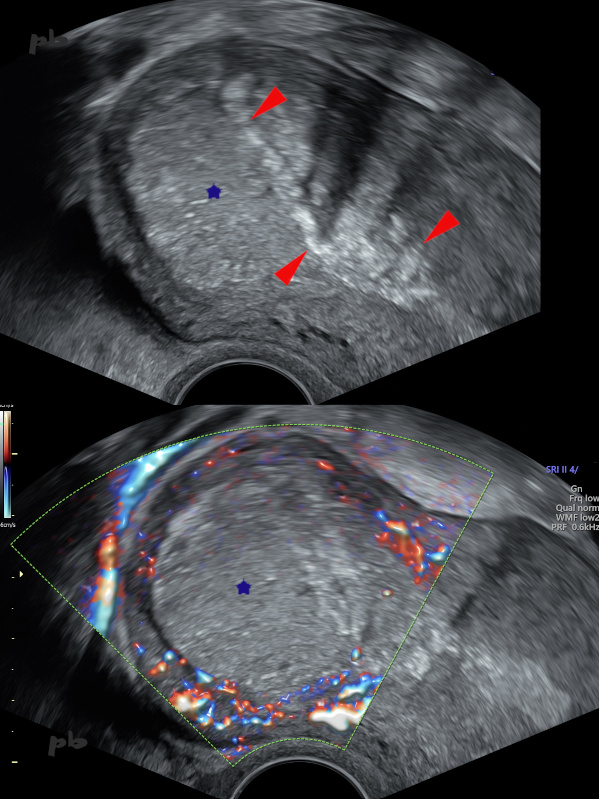

24 – Calcifications sur placenta acreta

Placenta acreta. Résidus placentaires laissés en place lors de l’accouchement (★).

Evolution attendue vers la régression, la dévascularisation (absence de flux en doppler couleur), et la calcification (►).